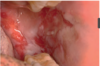

What is this infectious disease?

Necrotizing Gingivitis (NG)

o No periodontitis features

o SIMILAR APPEARANCE to gonorrhea

▪ Distinguishing characteristic of NG – Fetid Odor